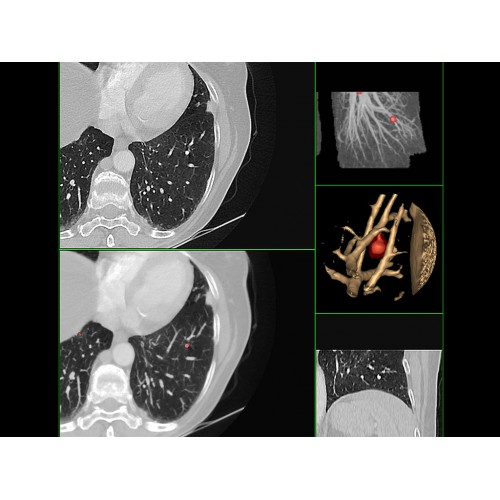

• Высокое качество изображения благодаря усовершенствованной системе реконструкции данных.

• Сниженная лучевая нагрузка на пациента без потери информативности снимков.

• Широкая область применения: от неврологии до кардиологии и онкологии.

Онкология

• Раннее выявление новообразований и контроль эффективности лечения.

• Планирование лучевой терапии с высокой точностью.

• 3D-реконструкция костных структур для планирования операций.